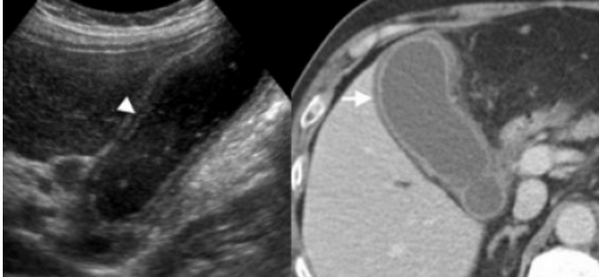

Сверху изображения пациента 62 лет с калькулезным холециститом. На УЗИ визуализируется стенки желчного пузыря растянутые, с субсерозным отеком (указано белыми стрелками) и в просвете желчного пузыря камень и взвесь. На КТ визуализируется переход воспалительного процесса с желчного пузыря на соседние ткани (перихолецистит).

74 — летнему мужчине выполнено УЗИ желчного пузыря. Диагноз: острый некалькулезный холецистит. На левой сонограмме стрелкой указано утолщение стенок желчного пузыря. В просвете желчного пузыря взвесь. На правой сонограмме у того же пациента при исследовании в доплеровском режиме выявлен еще один признак воспаления — гиперемия.